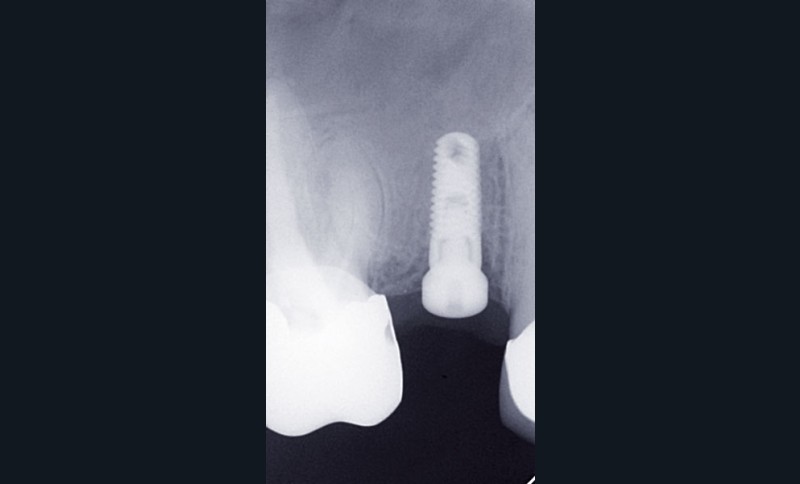

Le praticien s’assurera de la bonne intégration de l’implant avant la prise d’empreinte après examen clinique et radiographique (fig. 1).